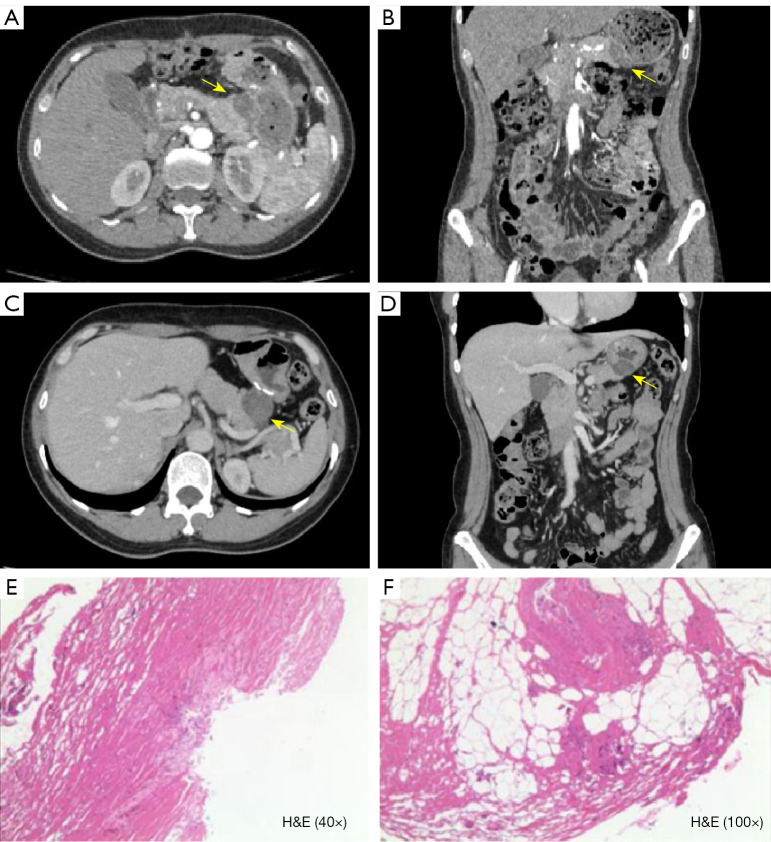

Results: A total of 168 fluorouracil implants were confirmed in the subdiaphragmatic regions, paracolic gutters, and tumor beds of 164 patients. Imaging features such as a typical foreign body reaction (85.71%), no contrast enhancement on CT/magnetic resonance imaging, and no diffusion restriction on diffusion-weighted imaging were important for differentiating between fluorouracil implant-related lesions and malignant lesions. Follow-up CT scans showed a size reduction in 67.26% of the lesions and density changes in 52.98%. The diagnostic accuracy and confidence of the radiologists were improved in stage 2 (accuracy: 91.25%; confidence: most often classified as medium) compared to stage 1 (accuracy: 67.5%; confidence: most often classified as low; both P<0.001). When surgical information was available, the diagnostic accuracy and confidence of the radiologists were improved in stage 3 (accuracy: 100%; confidence most often classified as high) compared to stage 2 (accuracy: P=0.007; confidence: P<0.001).